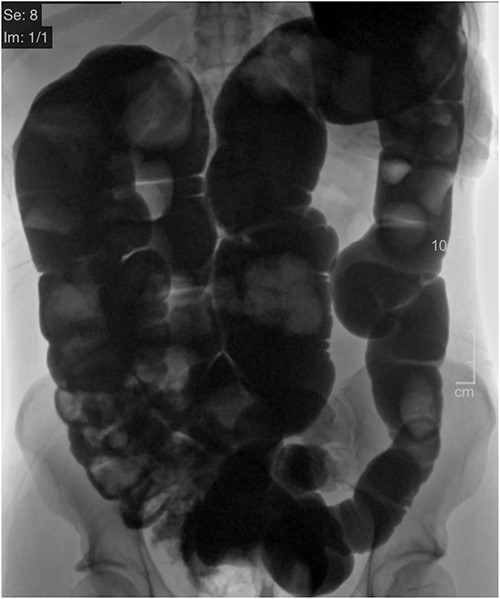

Two weeks following discharge, the patient completed a mechanical bowel prep and was admitted electively to undergo a colonoscopy and a laparoscopic extended right colectomy with anastomosis. Preoperative CT imaging depicted significant redundancy of the large intestine without evidence of obstruction or mass (Fig. 2). The transverse colon was resected ~15 cm (5.91 inches) proximal to the splenic flexure and 6 cm (2.36 inches) proximal to the ileocecal valve. A stapled side-to-side functional end-to-end anastomosis was created. The resected colonic specimen measured 80 cm (2.62 ft) in length, and 95 cm (8.62 ft) when stretched (Fig. 3). The patient was discharged 3 days later upon regaining bowel function. Six months later, the patient reported improved quality of life with minimal constipation, abdominal discomfort, and bloating.

CT Diatrizoate meglumine (DM) enema with air contrast. DM flows in a retrograde manner from the rectum to the cecum without evidence of obstruction or mass.